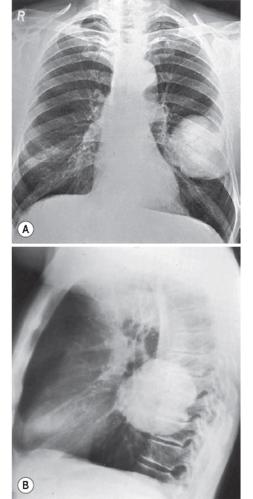

胸腔积液胸片典型图片

胸腔积液胸片表现图片